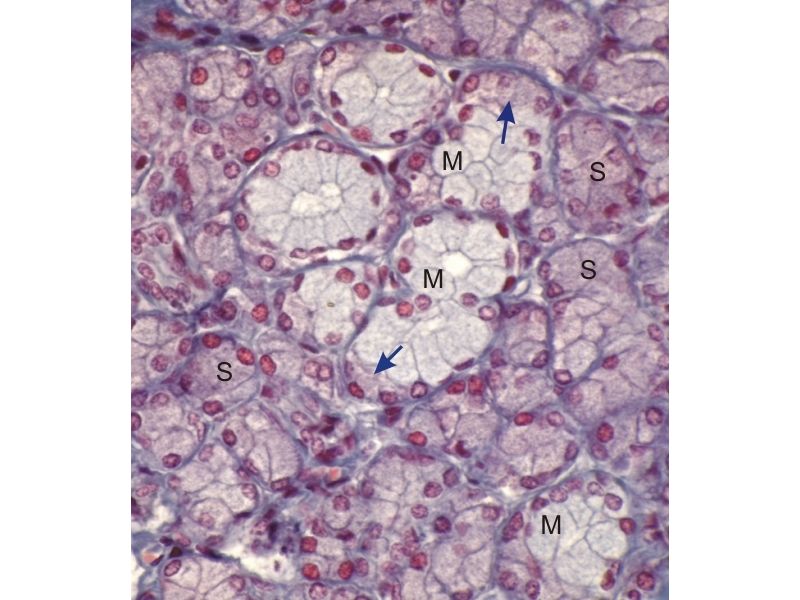

Mammary gland - slide 57